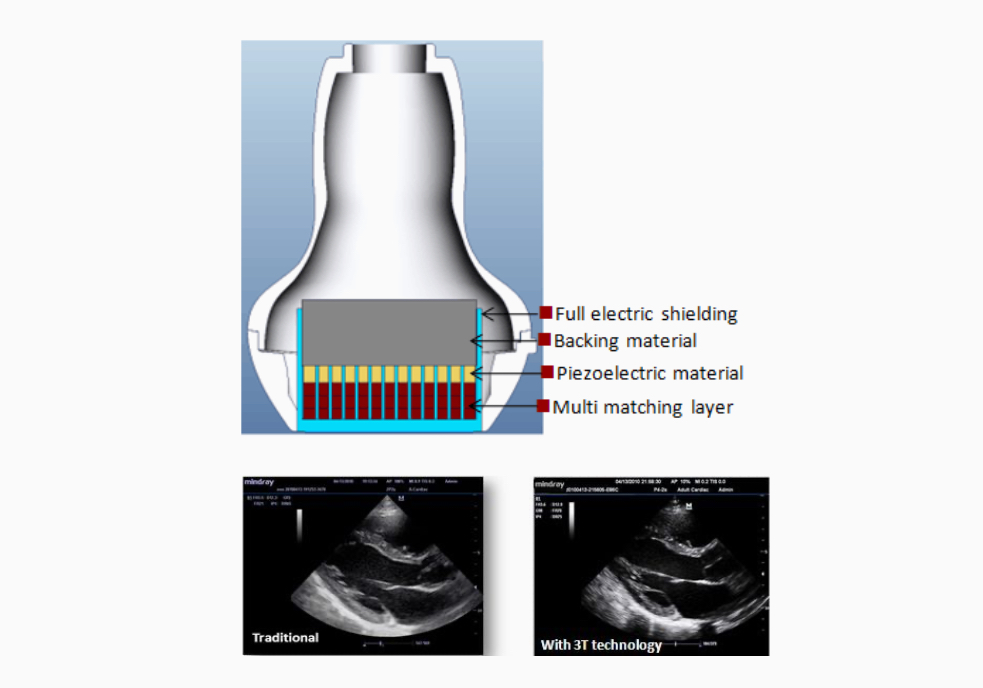

3T Transducer Technology

MindrayŌĆÖs patent transducer technology to increase image bandwidth and transmission efficiency.┬Ę Triple-matching layer design for higher sensitivity, wider bandwidth, and improved S/N.

┬Ę Total-cut design for lower cross-talk noise, better directivity, and improved lateral resolution

┬Ę Thermal-control design for better acoustic transmission